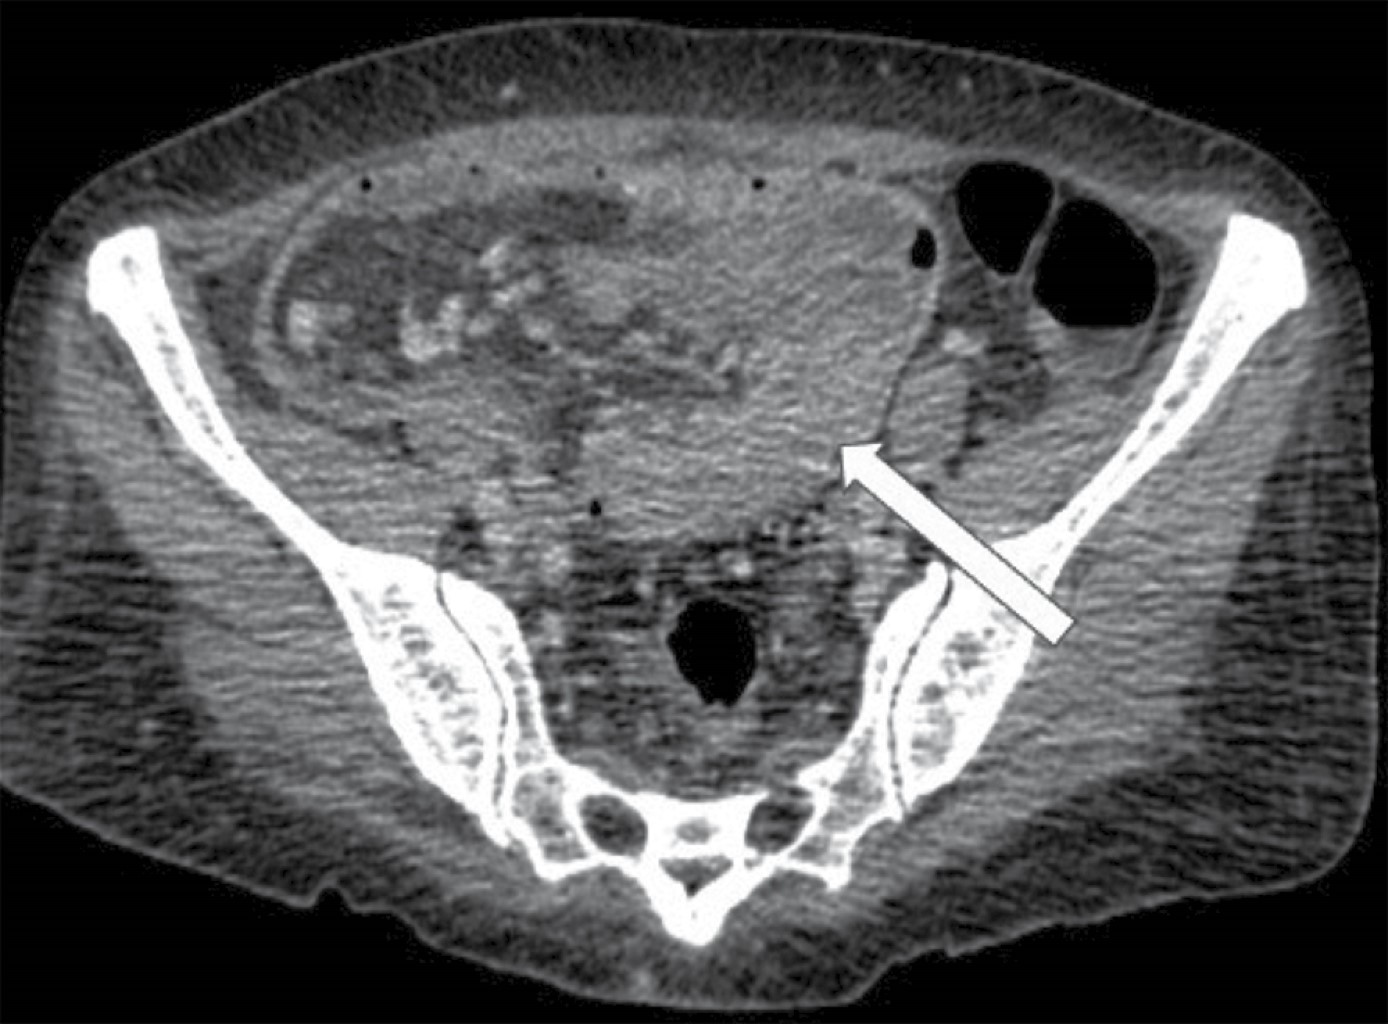

Figure 1